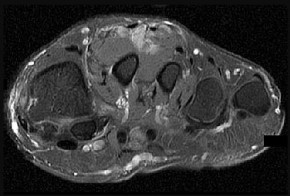

Surgical repair of the injury shown in the MRI scans in Figures 1 through 4 through a single-incision approach has a higher incidence of

The MRI scans show a distal biceps tendon avulsion with significant retraction. When addressing these injuries, a single-incision approach has been associated with an increased risk of lateral antebrachial cutaneous nerve injury. A two-incision approach has been associated with an increased risk of heterotopic ossification, second surgeries and posterior interosseous nerve injury.